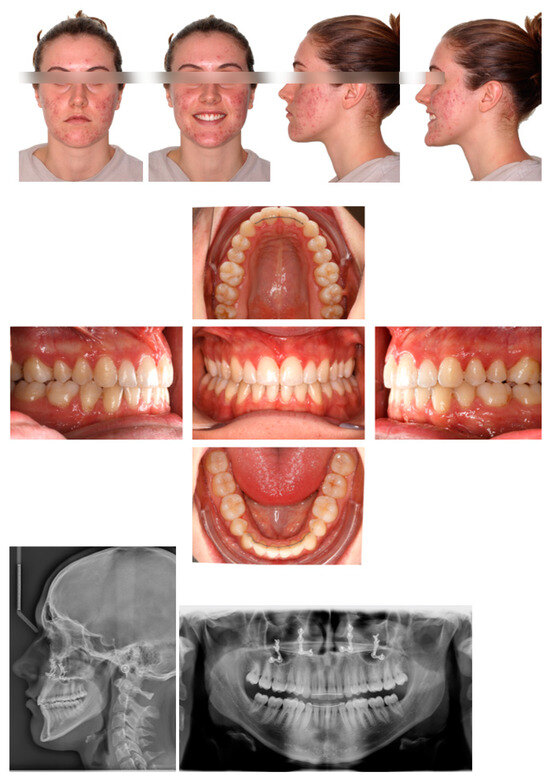

2.1. Diagnosis and Individual Treatment Planning

2.2. Clinical Preparations

2.4. Post-Operative Orthodontic Phase